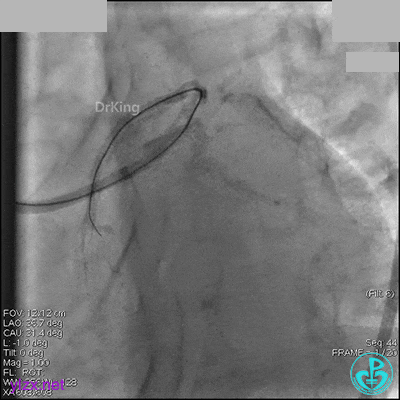

右冠脉中段充分扩张后欲植入3.5×38mm支架时,支架难以通过中远段扭曲处,且指引导管、导丝弹出飞扬。反复尝试导丝重新到达右冠脉远端时通过不顺利,局部造影剂滞留,远端血流接近3级。

右冠脉血流3级,患者无症状,终止手术。